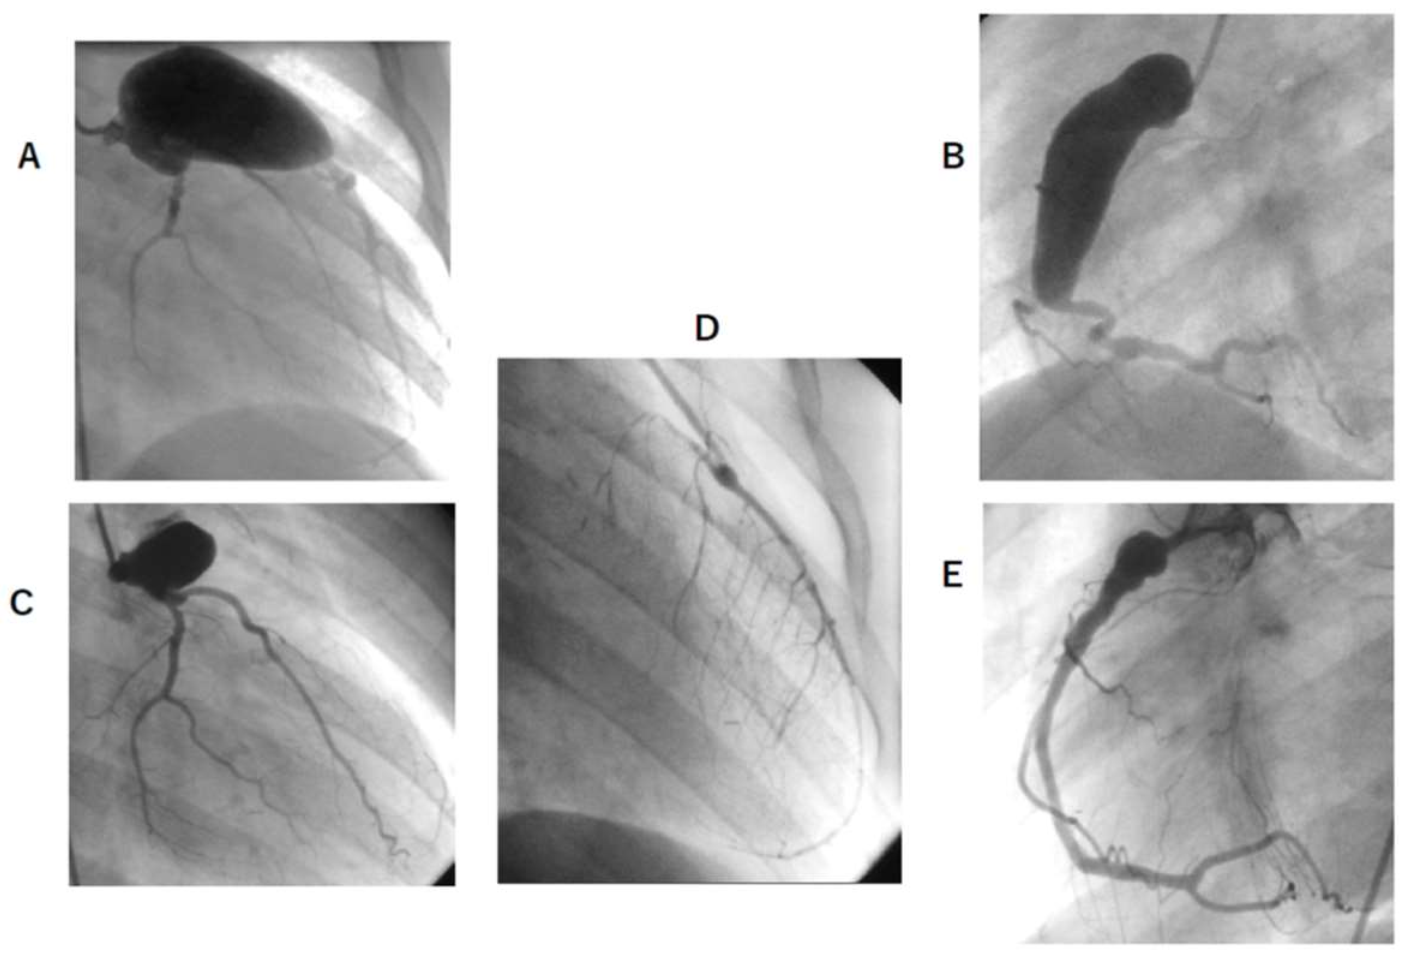

3.4. Latest CAG Findings